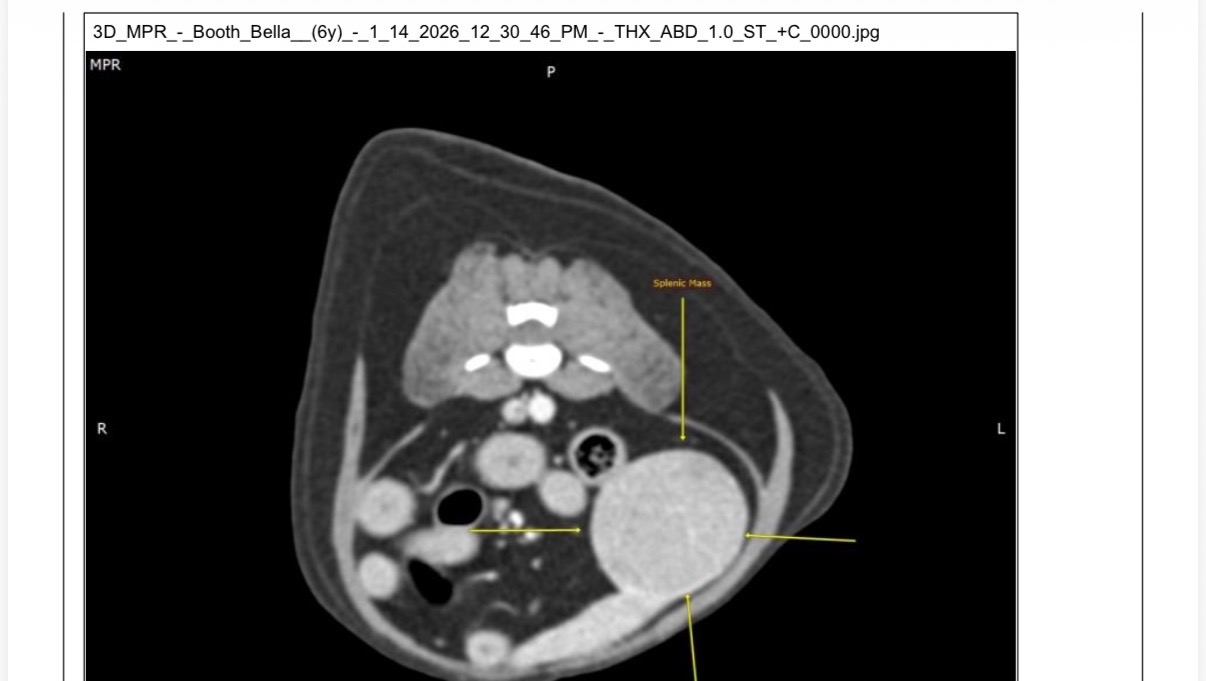

Recently, Bella became very ill. After extensive & expensive imaging, we received devastating news: she has a tennis ball–sized tumor on her spleen. She is in significant pain and without surgery she will not survive.

The only chance to save her life is surgical intervention immediately to prevent the large tumor from rupturing her spleen which would cause her to bleed internally. This is something she would not survive from.